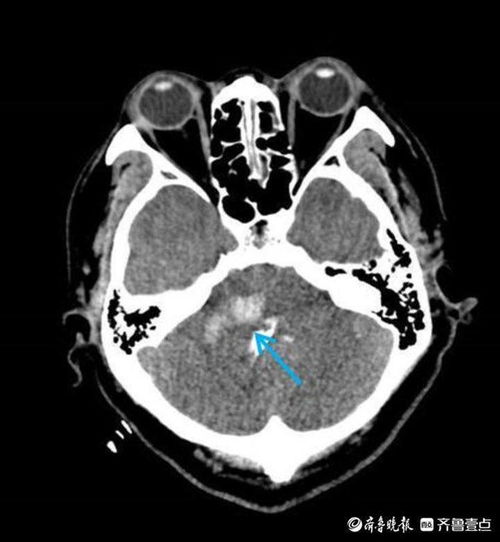

脑瘤是一种常见的神经系统肿瘤,这种疾病一旦发作,其危害性不言而喻。所以,人们对于脑瘤一直都是非常敬而远之的。但是,我们今天要讲述的却是一个名叫“瘤男”的男子,他成功逆袭,挽回了自己那失落的生命。

以前的瘤男原本是一个阳光开朗的青年,可是一次体检却让他的生命发生了翻天覆地的改变。医生告诉他,他患上了脑瘤,而且是晚期的。这个消息让他非常的恐惧和不安,他开始变得沉默寡言,脆弱敏感,甚至彻底失去了对生命的信心和勇气。